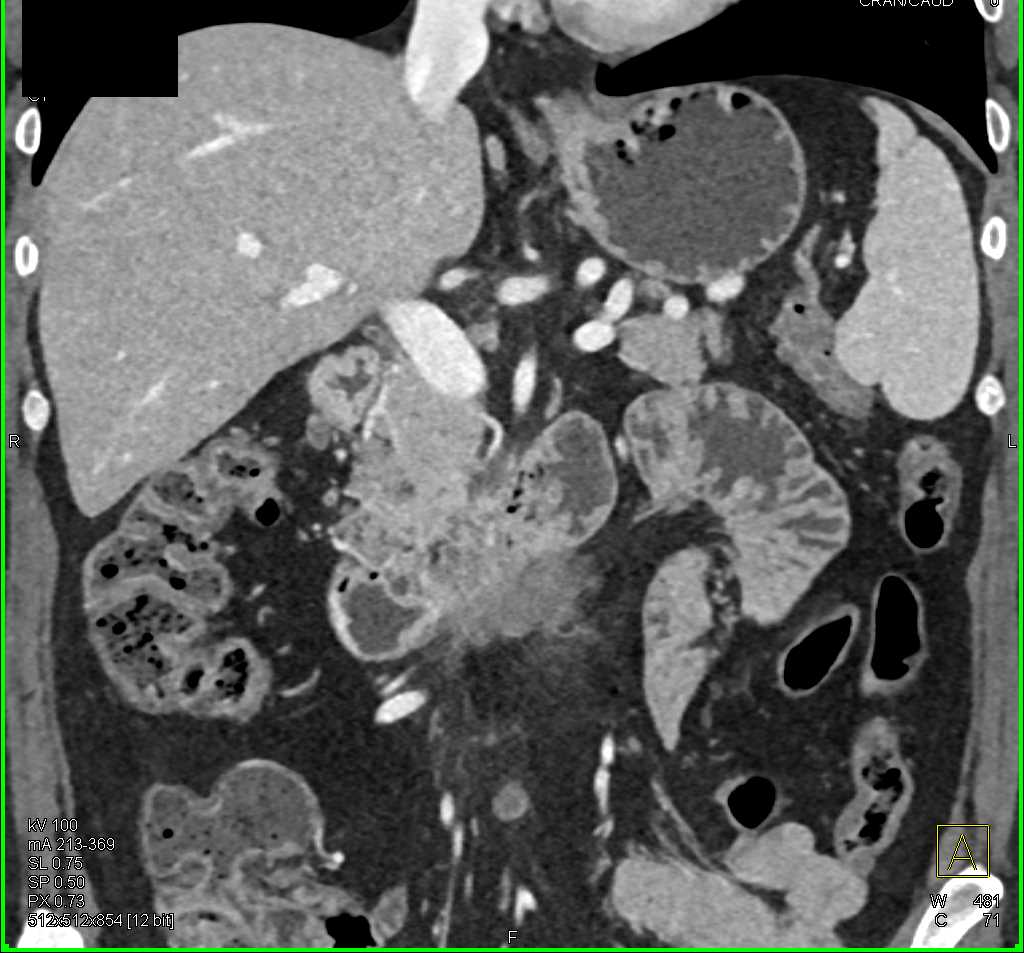

Duodenal Carcinoma with Obstruction